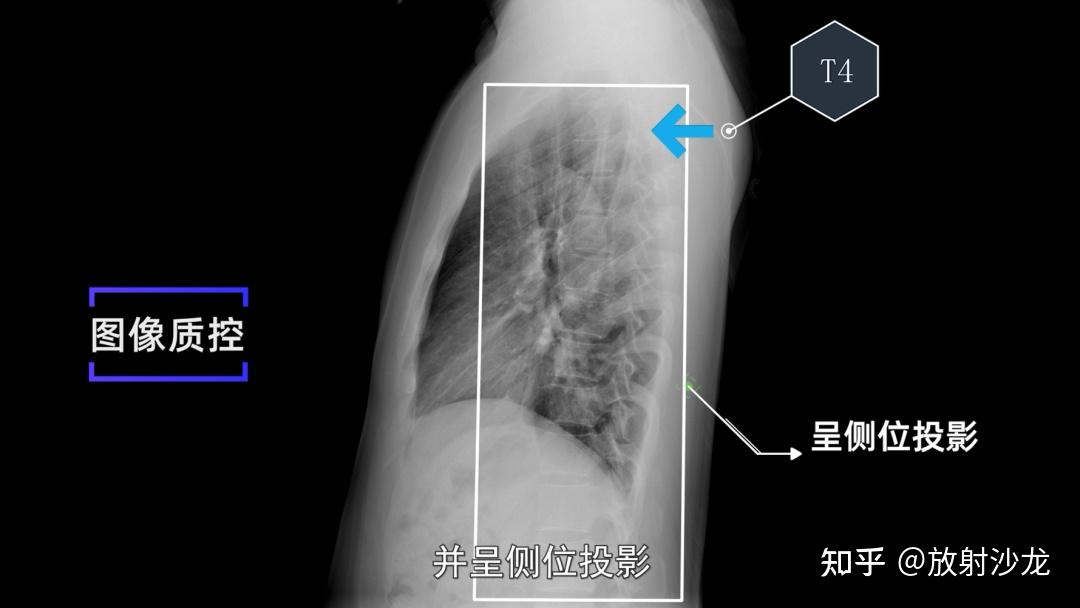

胸椎侧位如何看是第几胸椎?